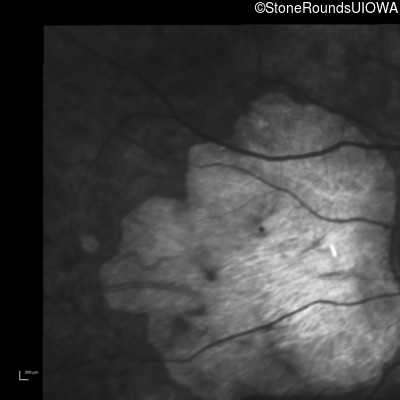

Infrared Fundus Photograph - Right - 20/150

Exemplar